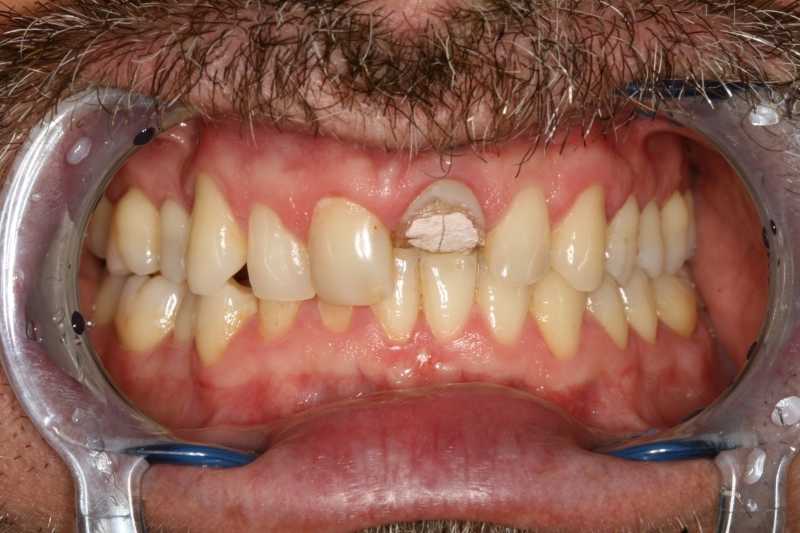

45 éves férfipáciensünk a képen látható státusszal érkezett klinikánkra: letört és nem korrekt gyökértöméssel rendelkező bal felső nagymetszővel, ill. régi, elszíneződött töméssel bíró, formáját tekintve kedvezőtlen esztétikájú jobb felső nagymetsző foggal.

Kiindulási állapot